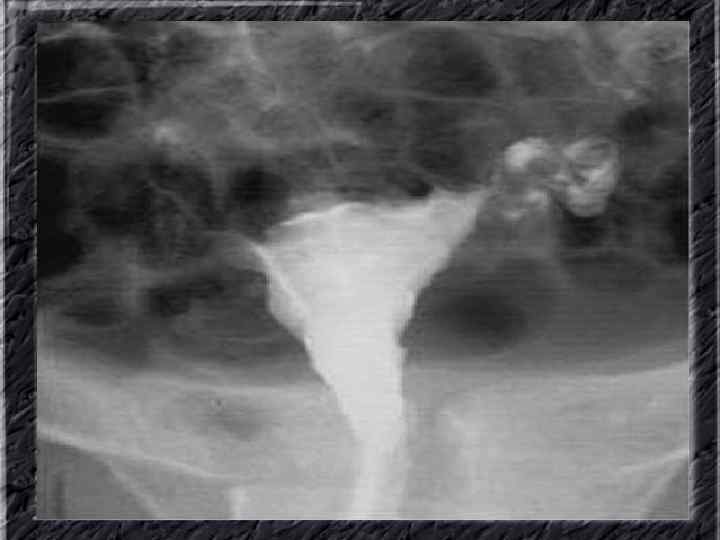

Названия слайдов: • • • Слайд 11. Гиперплазия эндометрия: железистый полип с очагами геморрагий; макропрепарат. Слайд 12. Ультрасонография: однородный эндометрий средней плотности с четкими ровными контурами при неактивной форме железистой гиперплазии эндометрия. Слайд 13. Ультрасонография: гипоэхогенная зона округлой формы в эхоизображении эндометрия — железистый полип. Слайд 14. Ультрасонография: железистый полип эндометрия в виде эхонегативного образования. Слайд 15. Гистерография: характерные изменения контуров полости матки при железистой гиперплазии эндометрия. Слайд 16. Гистерография: изменение формы и зубчатость контуров полости матки при эндометриозе. Слайд 17. Гистерография: изменение формы и зубчатость контуров полости матки при эндометриозе. Слайд 18. Гистерография: направленные перпендикулярно к контурам полости матки контрастированные канальцы. Слайд 19. Гистерография: затек рентгеноконтрастного вещества в правом углу матки при эндометриозе.